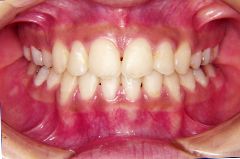

装置装着前

装置装着後